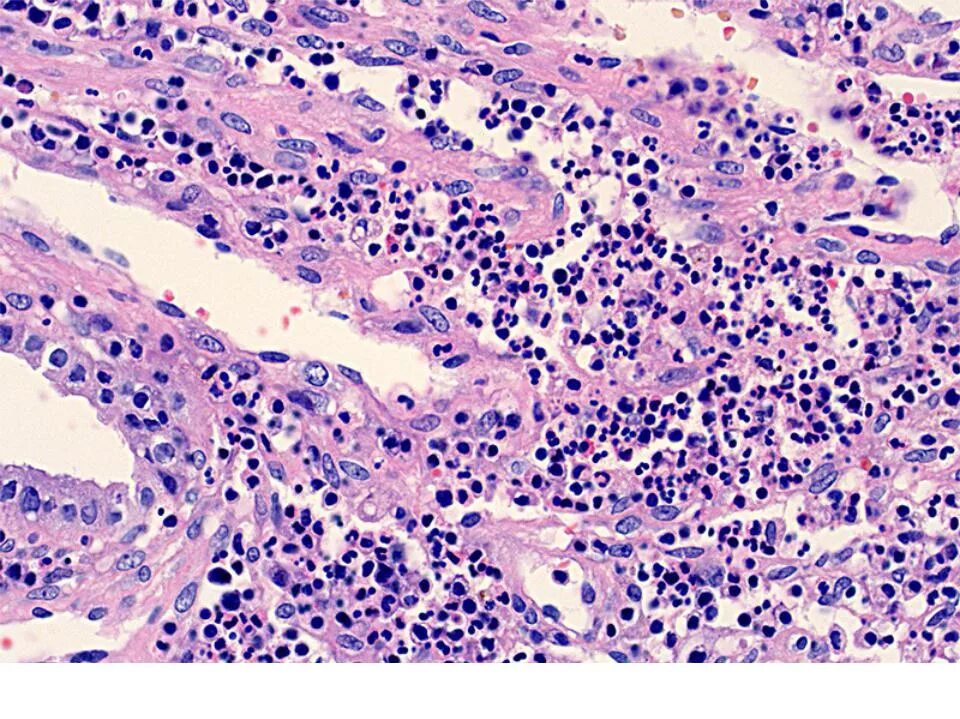

Эндометрит гистология